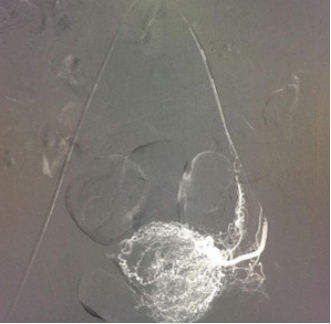

图5:子宫动脉栓塞后造影,子宫动脉主干、包括支配卵巢和阴道的血管保留,子宫染色消失。

子宫动脉栓塞术:是通过介入方法用栓塞物(如明胶海绵)将子宫动脉栓塞,以达到快速止血的作用。主要用于子宫急性大量出血时可行急诊栓塞,也用于异位妊娠出血,瘢痕子宫胎盘植入清宫术前预防出血。它作为一个有效的止血微创手术,为产科止血又提供了一个有效手段;它作为一种血管介入手术,无需开刀,损伤小,通过股动脉穿刺,超选择性插管术,将造影导管超选进入子宫动脉(如图4),再用明胶海绵栓塞子宫动脉以达到止血作用(如图5)。

由于考虑到年轻女性可能有再生育的需求,所以一般首选明胶海绵(>500um)进行栓塞。明胶海绵作为中期栓塞材料,能在30天左右自动被机体吸收再通,不会对患者子宫、卵巢的血管造成长期栓塞,不会影响患者以后的月经及再次怀孕,且原出血点经过一段时间的治疗恢复不再出血,从而达到治疗子宫瘢痕妊娠清宫出血过多和保护子宫的目的。